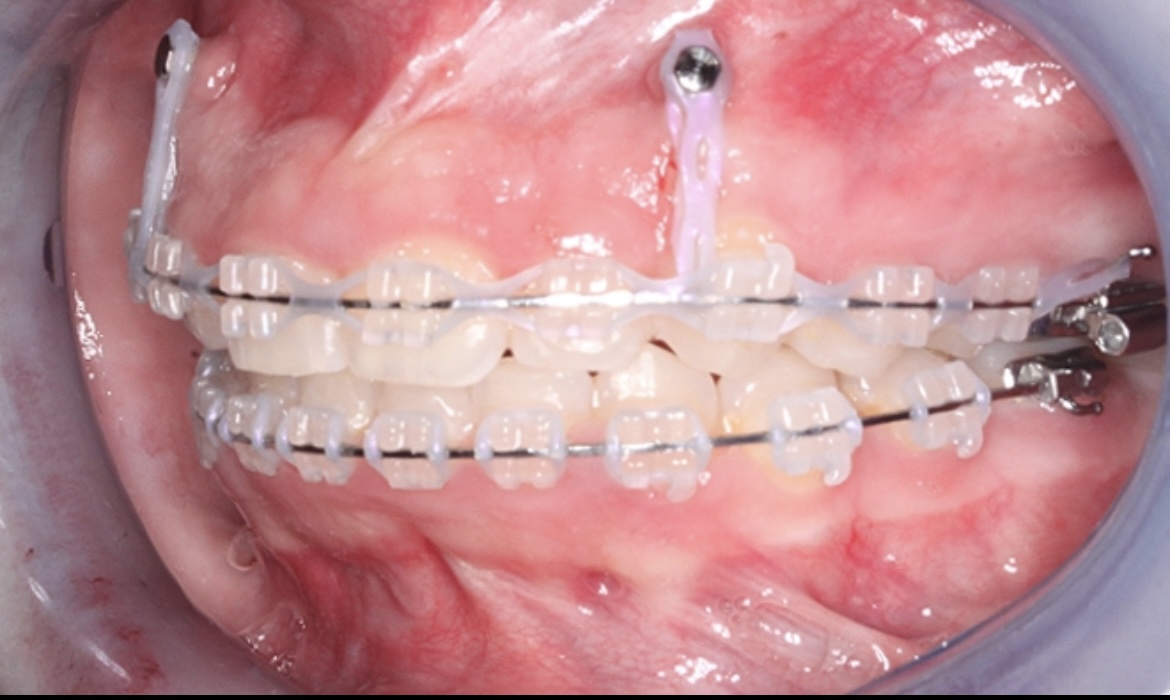

تقويم الأسنان

-

أو جراحة تصحيح الفك (نادرًا)